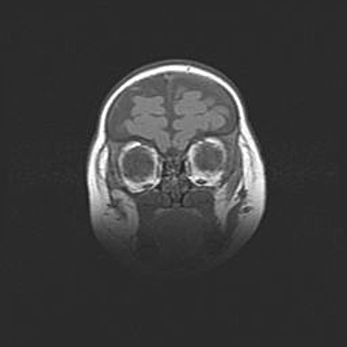

Множественные кисты обоих полушарий головного мозга, наибольшая из них в правой затылочной области. Ассиметричная атрофическая гидроцефалия.

Возраст: 7 месяцев

Вес: 5660 г

Пол: мужской

Окружность головы: 41,5 см

Срок гестации: 28-29 недель

Кисты головного мозга развиваются в результате многоочаговых некрозов вещества мозга и возникают вследствие перенесенной перинатальной инфекции, менингитов, энцефалитов, асфиксии, родовой травмы, расстройств мозгового кровообращения различного генеза. Образованию кист в веществе головного мозга плодов и новорожденных способствуют такие факторы, как высокое содержание в нем воды, недостаточная (или отсутствие) миелинизация и слабая астроглиальная реакция на повреждение.

Кисты могут сочетаться с гидроцефалией и другими поражениями головного мозга.